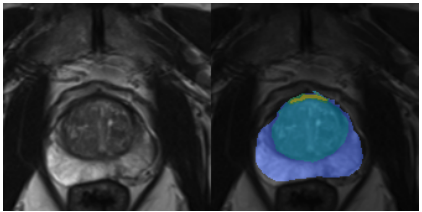

|   | On the Stability of Neural Segmentation in Radiology Moritz Wolter, Lokesh Veeramacheneni, Bettina Baeßler, Ulrike I Attenberger, Barbara D Wichtmann

European Symposium on Artificial Neural Networks, Computational Intelligence and Machine Learning, ESANN 2024

Paper

/

Code